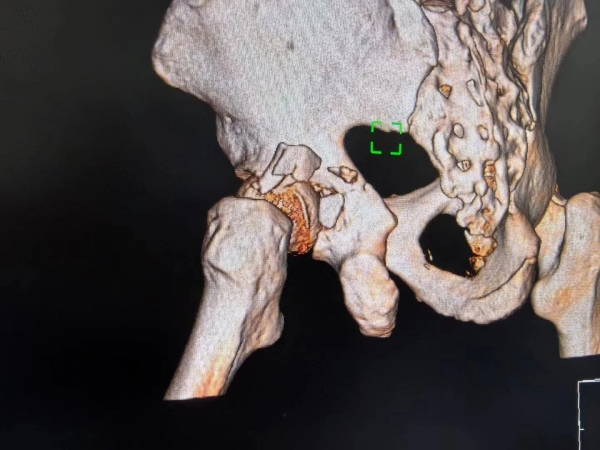

941 瀏覽“燕主任,你看,我能下獨(dú)立走了,走得還挺穩(wěn)的,謝謝了”,已出院的應(yīng)大爺在視頻里露出燦爛的笑容,激動(dòng)地向燕主任發(fā)來(lái)康復(fù)的喜訊?!安焕⑹枪强茖<?,這樣難度的手術(shù),學(xué)到了”,外一科的醫(yī)生邊看視頻邊感慨到。

“外一科有燕主任在,是我們的榮幸,是患者的福音啊”,行政主任丁廣甫總這樣提到。這位肩挑重任,以仁心撐起“生命支柱”的燕主任就是骨科專家創(chuàng)傷主任燕冰。